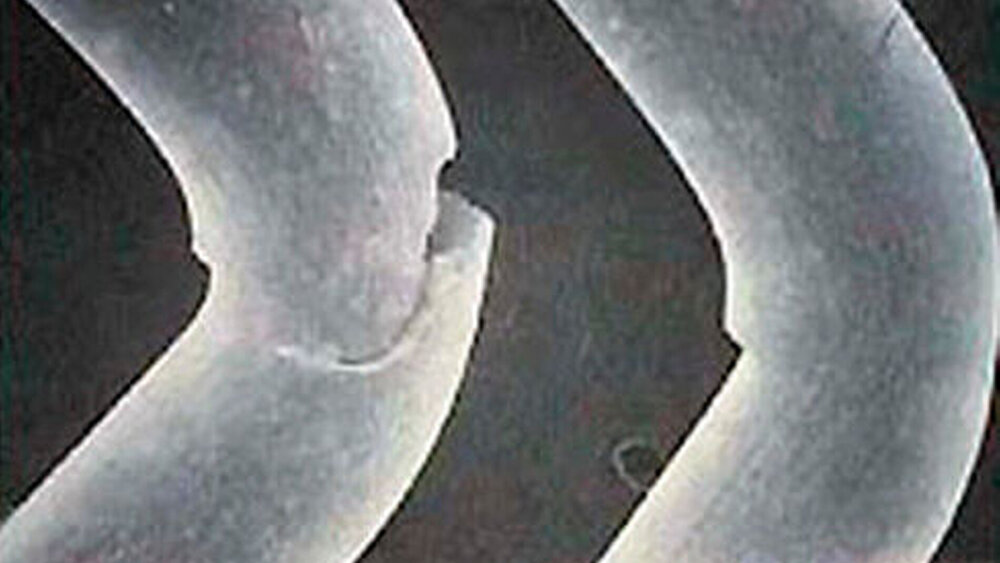

Die innovative Kombination aus weißem Faden und schwarzer Nadel ermöglicht exzellente Sichtbarkeit im OP-Gebiet. DirectFlon ist ein monofiles Nahtmaterial. Die glatte Oberfläche verhindert die Akkumulation von Bakterien und Essensresten. Im Gegensatz zu anderen Nahtmaterialien verhindern die Enden des PTFE-Fadens Irritationen an den Schleimhäuten.